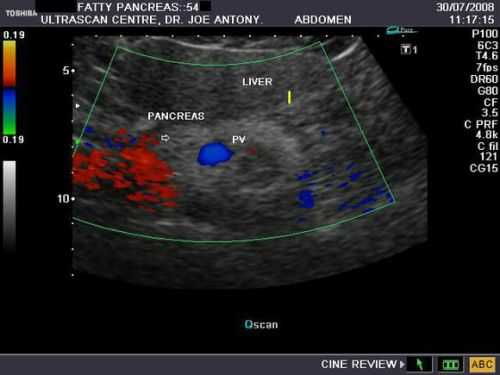

Кроме этого, врач изучает состояние сосудов, располагающихся внутри органа и возле него, что позволяет дать оценку кровоснабжения железы. В случае, если при исследовании поджелудочной железы на УЗИ были выявлены какие-либо отклонения от нормы, врачом проводятся различия между аномалиями железы. Перед ним стоит нелегкая задача отличить воспаление от опухоли, возрастные изменения в органе от хронического панкреатита и т.д.

- Дольчатая поджелудочнfz. Характеризуется замещением здоровых клеток железы на жировую ткань и повышенной эхогенностью. При таком состоянии поджелудочная на мониторе выглядит намного светлее.